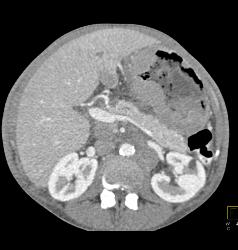

Gastric Lymphoma With Nodes and Ulceration